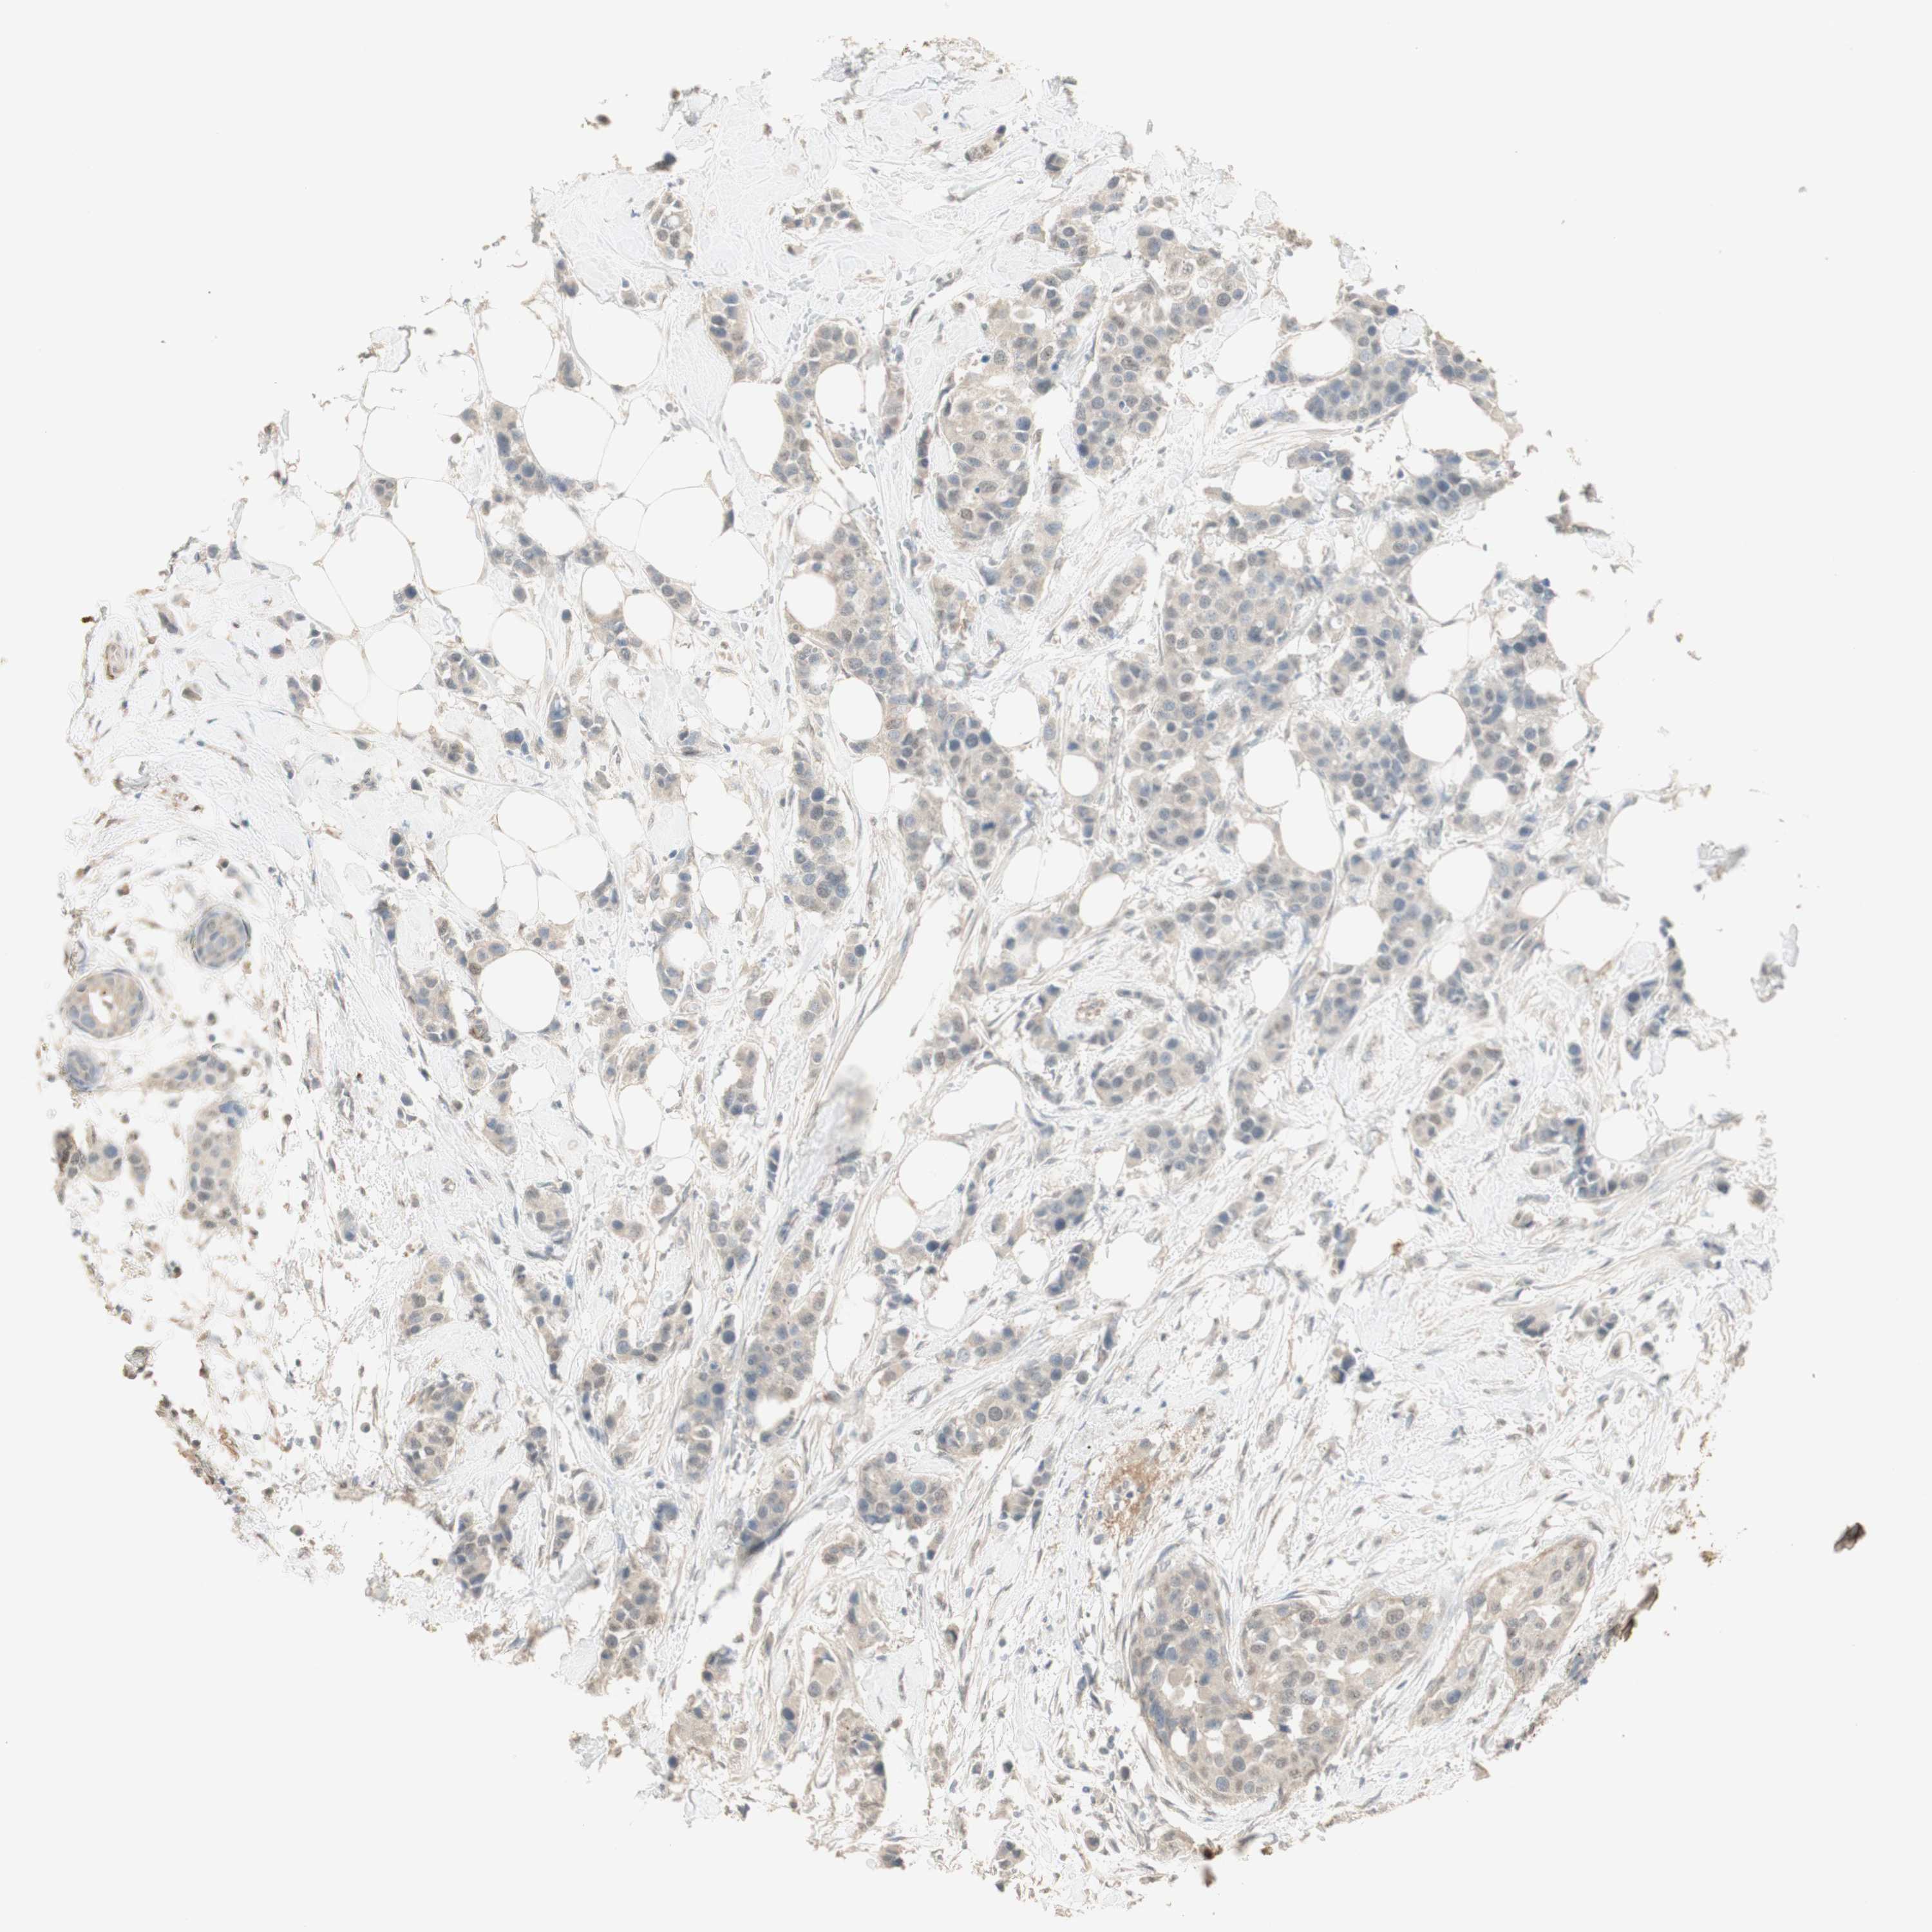

BRCA TCGA BRCA VALIDATION PROTEIN EXPRESSION

ANTIBODIES

AND

VALIDATION